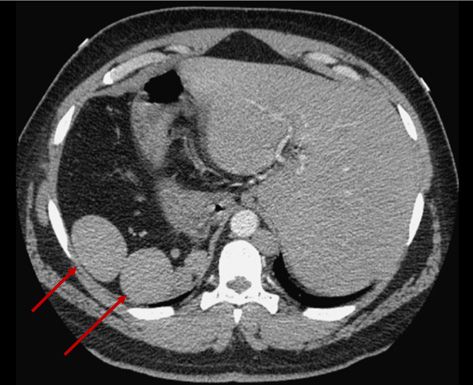

Physical examination revealed right upper quadrant abdominal tenderness, but no pallor, jaundice, or scleral icterus. No cardiac, respiratory, or neurologic abnormalities were found. Chest films and full body CT scans were significant for situs inversus totalis with polysplenia (multiple small spleens1). The chest radiograph, Figure at left, shows the dextrocardia that is characterisitc of situs inversus totalis. Polysplenia is seen (arrows) on the abdominal CT scan, Figure below. A white blood cell (WBC) count with differential revealed a slight leukocytosis (leukocyte count, 13 x 103/µL), but all other values were within normal limits. Following 2 days of supportive treatment, the patient’s temperature spiked, peaking at 41oC (106.1oF) despite interval increase in antipyretics and use of cooling blankets. The WBC count increased to 23 x 103/µL while the patient was receiving empiric antibiotic treatment with vancomycin, ceftriaxone, and metronidazole. Multiple blood cultures; tests for influenza A and B antigens, H1N1 antigen, and Clostridium difficile toxin; stool guaiac test; hepatitis panel; urine culture; and stool cultures for Giardia, Cryptosporidium, and ova and parasites all yielded negative results.

This patient’s impaired immunity was believed to be the result of functional asplenia, a condition secondary to polysplenia associated with situs inversus totalis.4 Functional asplenia renders the body susceptible to fulminant infection from specific pathogens.5 Infections with encapsulated organisms are most common, but Pseudomonas infections also occur frequently.6 In our patient, the diagnosis of Pseudomonas enteritis was supported by stool culture isolates, demonstrated physiologic predisposition, and rapid resolution of symptoms following administration of appropriate antimicrobials.